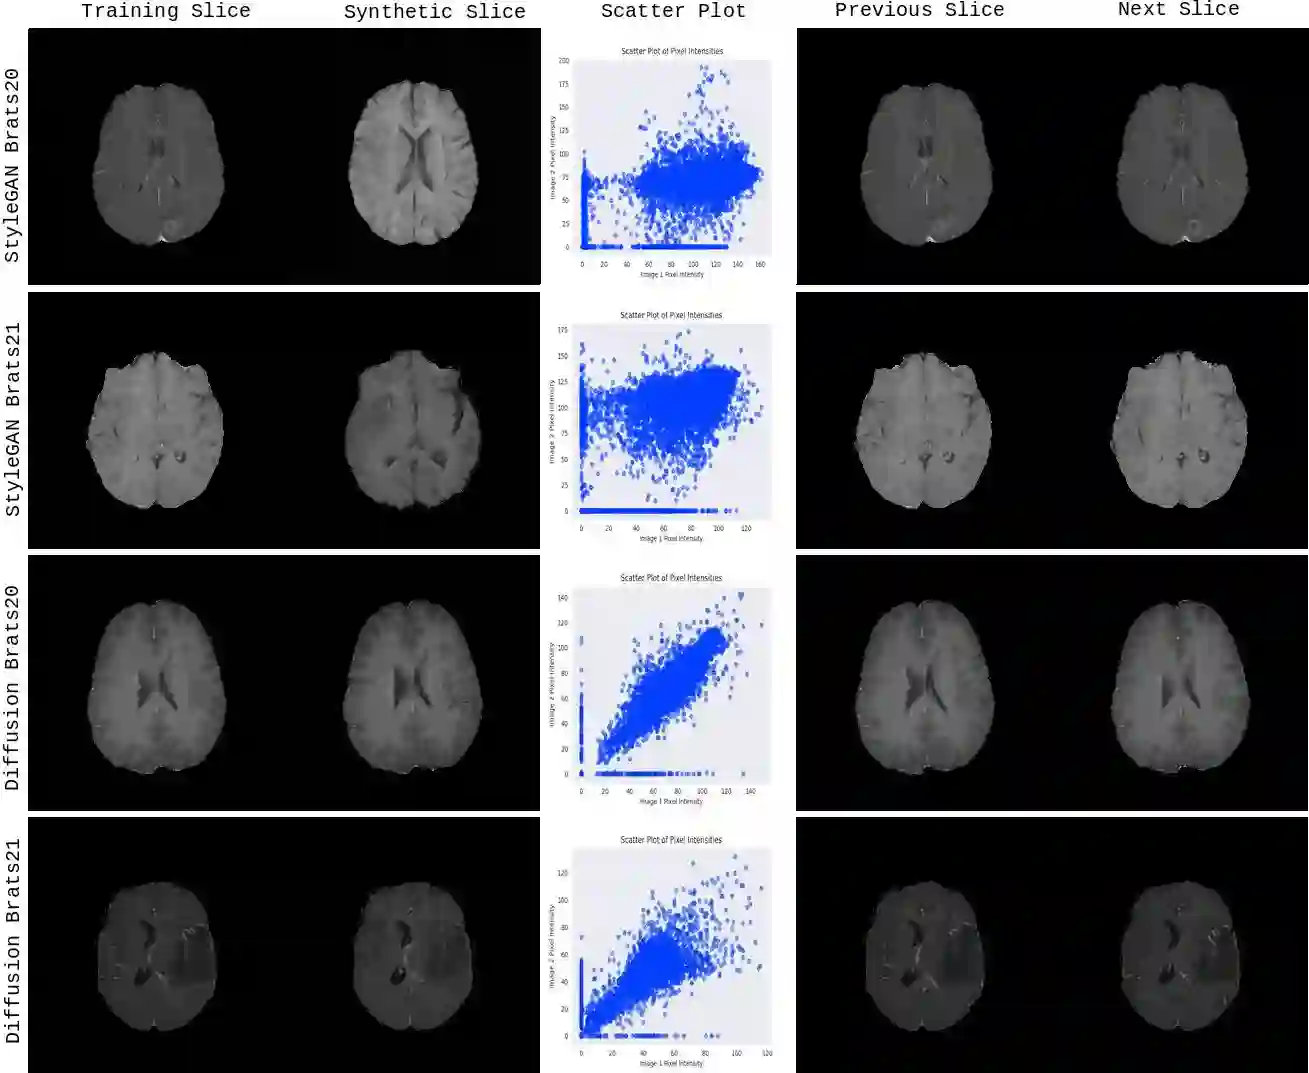

Diffusion models were initially developed for text-to-image generation and are now being utilized to generate high quality synthetic images. Preceded by GANs, diffusion models have shown impressive results using various evaluation metrics. However, commonly used metrics such as FID and IS are not suitable for determining whether diffusion models are simply reproducing the training images. Here we train StyleGAN and diffusion models, using BRATS20 and BRATS21 datasets, to synthesize brain tumor images, and measure the correlation between the synthetic images and all training images. Our results show that diffusion models are much more likely to memorize the training images, especially for small datasets. Researchers should be careful when using diffusion models for medical imaging, if the final goal is to share the synthetic images.